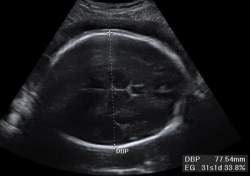

Medición del diámetro biparietal

En la ecografía 2D del tercer trimestre de embarazo se puede hacer la medición del diámetro biparietal, que es la distancia que existe entre los huesos parietales del cráneo. Esta medida es una buena referencia del crecimiento fetal. En la imagen, esta medida aparece acotada por una línea...